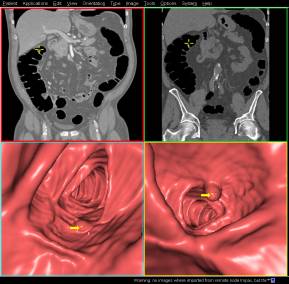

7 . CT 仿真内窥镜

CT 仿真内窥镜软件是在 CT 扫描容积数据的基础上,借助于不同介质,组织之间的密度差别和 SSD , VRT 的自动重建与导航技术,虚拟再现内窥镜观察效果。可广泛用于空腔脏器的模拟内窥镜成像,如消化道,气道,鼻窦等;还可以用于血管结构的腔内显示。由于 16 层 CT 所具有的超高分辨率各各向同性成像优势,即使如冠状动脉末梢,内耳等处, CT 仿真内窥镜也能进退自如。目前 CT 仿真内窥镜在临床上应用最多的是用于结肠小息肉诊断和早期结肠癌的普查。

结肠内窥镜